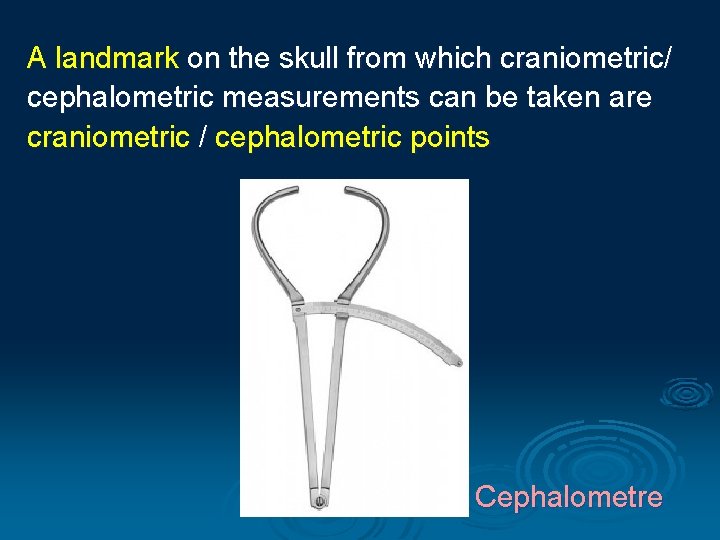

A landmark on the skull from which craniometric/ cephalometric measurements can be taken are craniometric / cephalometric points Cephalometre